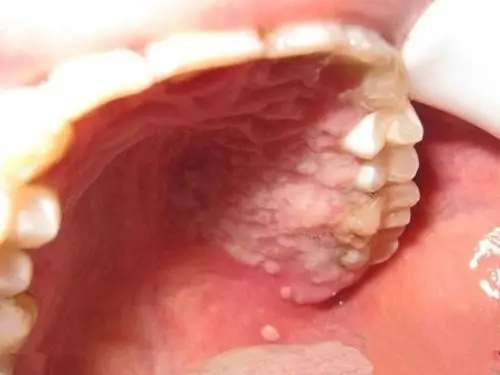

难治的口腔粘膜白斑是何物?

口腔白斑

口腔白斑病

求助急求各位高手帮忙诊断是否口腔白斑